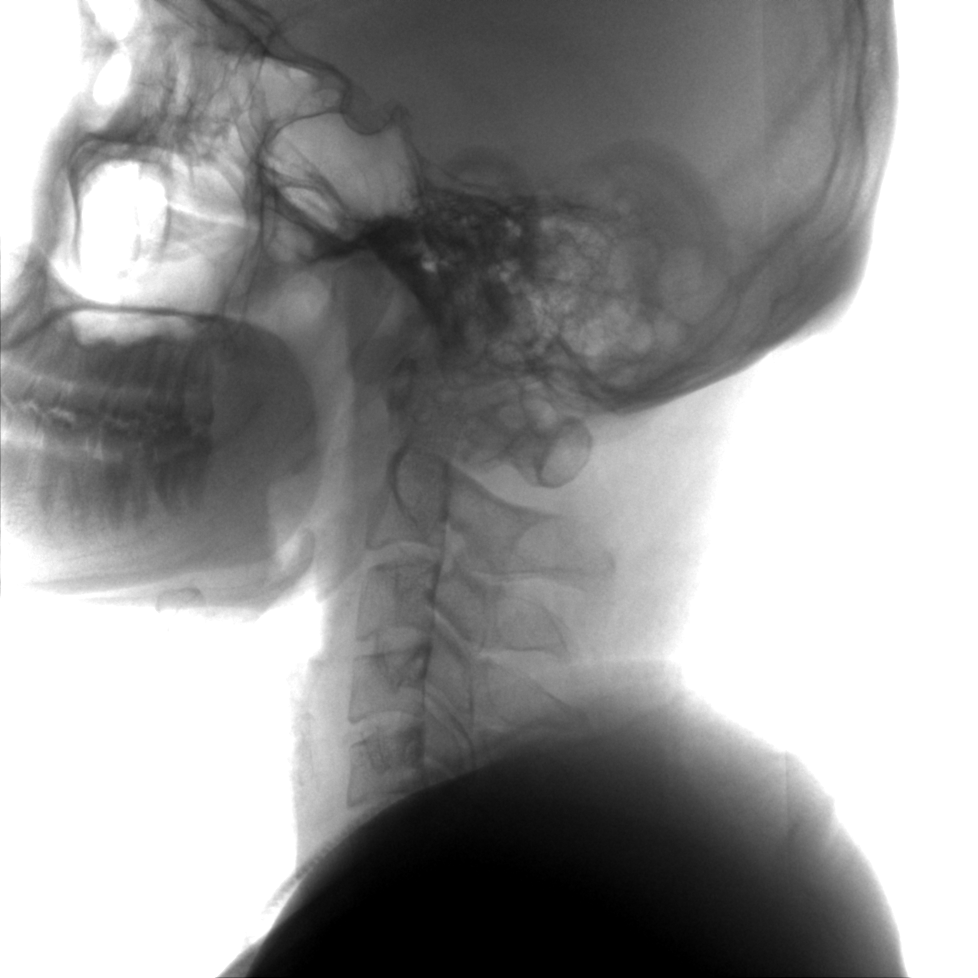

術(shù)中三維成像和橫斷面圖像提供多角度的手術(shù)診斷信息,輔助醫生進(jìn)行術(shù)中評估判斷,諸如骨折復位情況和內植入螺釘的尺寸和位置,輔助手術(shù)更好地完成。

提供更大的術(shù)中三維成像視野,采集更多圖像信息,可一次拍全全段頸椎、全段腰椎、七節胸椎、雙側骶髂關(guān)節、股骨頭及單側盆骨。